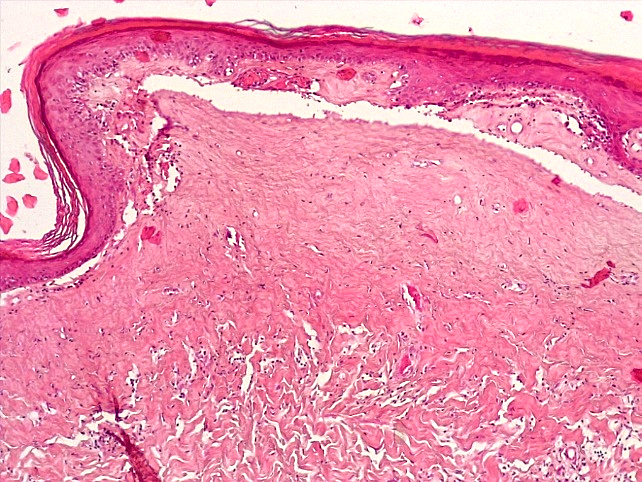

При морфологическом исследовании биоптатов вульвы пациенток с атрофическим вариантом течения СЛВ наибольшие изменения наблюдались со стороны эпидермиса и поверхностных слоев дермы. В эпидермисе отмечалась резкая атрофия клеток многослойного плоского эпителия (МПЭ) с участками повышенного ороговения (гиперкератоза и паракератоза), в некоторых случаях были выявлены участки фибриноидного некроза с окружающей лейкоцитарной клеточной инфильтрацией (рис. 1), указывающие на наличие очагов острого язвенного повреждения эпидермиса на фоне дистрофических и регрессивных изменений многослойного плоского эпителия. При этом количество клеточных слоев эпидермиса было уменьшено в среднем до 3–4 с избыточным образованием роговых чешуек в поверхностных слоях, а количество базальных клеток эпидермиса в 1 мкм не превышало 10, что свидетельствовало об атрофии резервного слоя эпидермиса (рис. 2).

Рис. 1. Атрофический вариант течения СЛ вульвы. Участок фибриноидного некроза с лейкоцитарной инфильтрацией многослойного плоского эпителия с развитием паракератоза, дискератоза. Развитие плотной волокнистой соединительной ткани в поверхностных слоях дермы с умеренной лимфо-гистиоцитарной инфильтрацией (окраска гематоксилином-эозином, х100)

Fig. 1. Atrophic variant of the course of the vulva SL. A site of fibrinoid necrosis with leukocyte infiltration of multilayer squamous epithelium with the development of parakeratosis, dyskeratosis Development of dense fibrous connective tissue in the superficial layers of the dermis with moderate